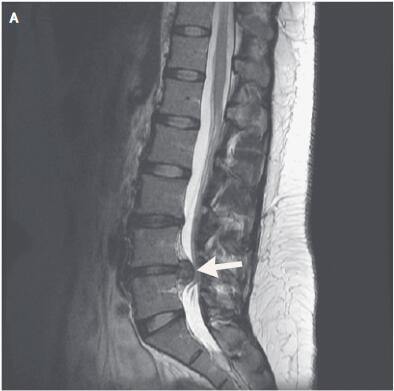

一名29岁的女性患者,6个月前开始出现右腿疼痛伴有感觉异常的症状,无大小便失禁。大约5个月前MRI(腰椎磁共振成像)显示:腰椎间盘突出导致椎管狭窄和神经根受压(如下图A,重点见箭头所指)。

该患者选择了

保守治疗:物理治疗和硬膜外注射糖皮质激素(主要是起抗炎和镇痛作用)。